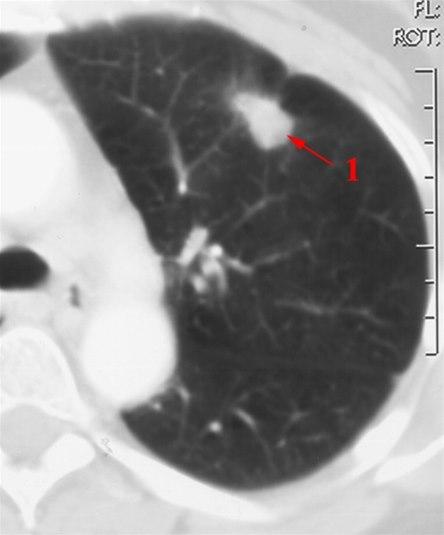

CT-bilde av lunge med svulstLungekreft er den kreftformen som tar flest liv i Norge, og den utgjør rundt en av ti nye krefttilfeller. Lungekreft omfatter alle kreftformer i lunger og/eller luftveier (bronkier). Omtrent én av ti av alle krefttilfeller i Norge er lungekreft. Av disse er de fleste såkalt bronkialkreft.

For å fastslå diagnosen er røntgen og CT av lungene nødvendige undersøkelser. Vanligvis får legen mistanke om lungekreft på grunnlag av sykehistorie og lungerøntgen. Utredningen fortsetter så med CT-undersøkelse. Da får man en langt mer presis beskrivelse av svulsten og dens forhold til omliggende vev. Vanligvis utvides CT-undersøkelsen til å omfatte CT også av lever og binyrer, fordi dette er organer som lungekreft tidlig kan spre seg til.